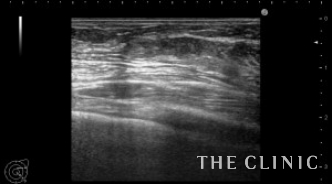

他院でヒアルロン酸豊胸を行った方ですが、炎症のためヒアルロン酸の周囲に非常に厚い被膜が形成され、瘢痕化していました。

しこりは両側の乳房全体にあり、一部は以前ヒアルロニダーゼで吸引しました。

被膜は肥厚して中心にわずかにヒアルロン酸があります。

ヒアルロニダーゼで溶解して吸引しましたが、被膜は残存しています。

エコーとの比較です。

このしこりは内腔がありヒアルロン酸がありました。

ヒアルロン酸注入によるしこりのエコー診断カルテ